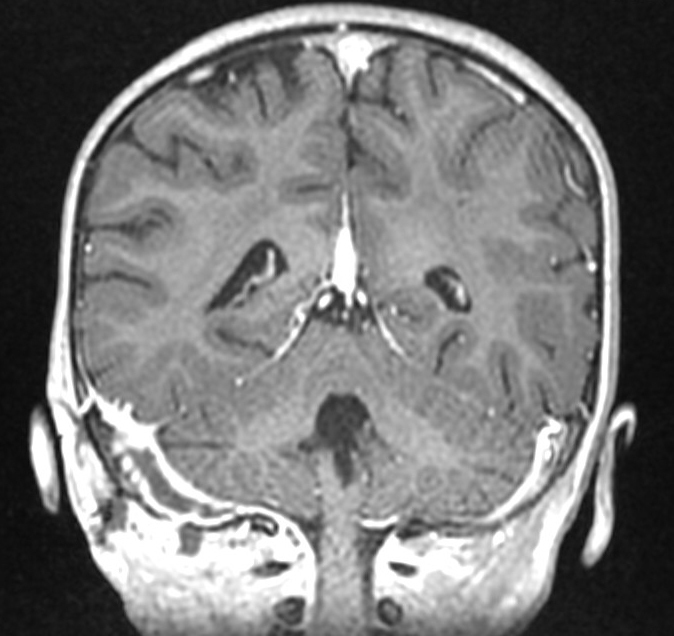

Voici l’imagerie que vous avez demandée. Devant le tableau, le radiologue a également choisi de faire une IRM.

Question 13 : Qu’en pensez-vous ?

Faux, la substance grise est grise, et la substance blanche est blanche (moyen mnémotechnique), c’est donc une séquence T1 (en T2, la substance grise apparaît en hypersignal). C’est ici un T1 avec injection de gadolinium

C’est une séquence T1 avec les vaisseaux en hypersignal franc. C’est donc un T1 avec injection de gadolinium

On peut voir sur le scanner une image très hypodense dans le sinus à droite (alors que le sinus gauche est normalement hyperdense). C’est très visible sur la coupe en IRM avec un caillot hypo-intense au milieu du sinus veineux à droite

Comme expliqué à la question précédente, l’intérêt est de chercher les complications intracrâniennes. Il n’y a pas ici d’abcès intracrânien, mais on retrouve une thrombophlébite importante du sinus sigmoïde droit. Insérer image « Figure10.jpg ». Insérer image « Figure11.jpg ». Insérer image « Figure12.jpg »